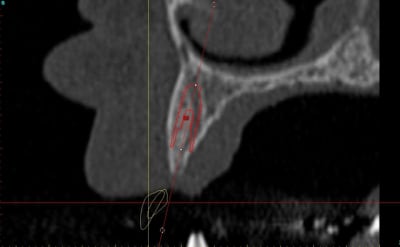

dentiste57 écrivait:

--------------------

> et là ?

> greffe selon ta méthode ?

Cross section dhvkc8 - Eugenol

3d dt3qom - Eugenol

Overview uqcp6u - Eugenol

> dentiste57 écrivait:

> --------------------

> > et là ?

> > greffe selon ta méthode ?

expansion, c'est plus cool!